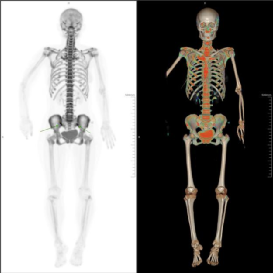

10 月 27日,四川泰康医院核医学科迎来技术应用又一重要时刻,当日成功开展18F-NaF PET/CT全身骨显像扫描检查。

而18F(氟-18)标记的氟化钠(NaF),是一种用于探测骨骼病变的PET显像剂,它具有高灵敏、亲骨性特性,为骨骼病变的精准诊断、鉴别和个体化治疗提供了更敏感、更可靠的支持!

(图源:科室扫描图)